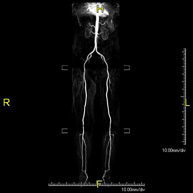

- Angio RM Arterial extremidades inferiores

Prueba diagnóstica no invasiva que consiste en el estudio vascular del sector aorto-ilíaco y de los vasos arteriales de ambas extremidades inferiores, obteniendo imágenes de alta definición anatómica mediante el empleo de un campo electromagnético y ondas de radio (con un emisor y un receptor). Es indispensable el uso de contraste paramagnético (Gadolinio). Sin embargo, no utiliza radiación ionizante. La calidad de las imágenes permite realizar reconstrucciones en 2D y 3D. Está especialmente indicado en aquellos pacientes en los que hay sospecha de enfermedad vascular de ambas extremidades, en pacientes con enfermedad vascular de ambas extremidades como el mapa vascular antes del tratamiento (percutáneo o quirúrgico), como el mapa vascular pre-quirúrgico en pacientes con lesiones óseas o musculares que requieran cirugía, etc.